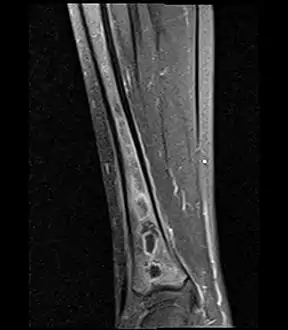

Coronal fat suppressed STIR image showing, bone marrow and subcutaneous edema as well as subperiosteal edema. The thin hypointense rim surrounding the intramedullary collection represents the reactive interface between the abscess and the body's attempt to wall it off.